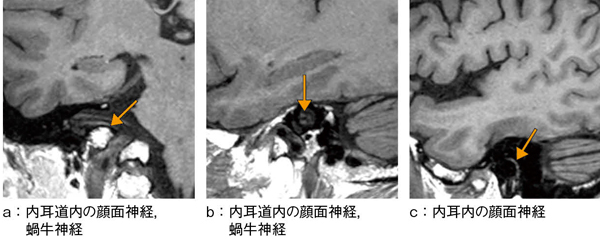

また,内耳および中耳領域では,内耳道内を走行する顔面神経や蝸牛神経が冠状断像および矢状断像にて良好に描出されている(図3 a,b)ほか,中耳を走行する顔面神経もとらえられている(図3 c)。これは,磁化率効果に弱いgradient echo系のシーケンスでは描出されにくい構造であり,SE系のシーケンスの大きな特長である。この領域でしっかりとしたコントラストが得られることにより,感染による炎症等を評価するための造影検査に大きな力を発揮すると期待している。

図3 isoFSE T1強調画像(内耳・中耳領域の拡大)